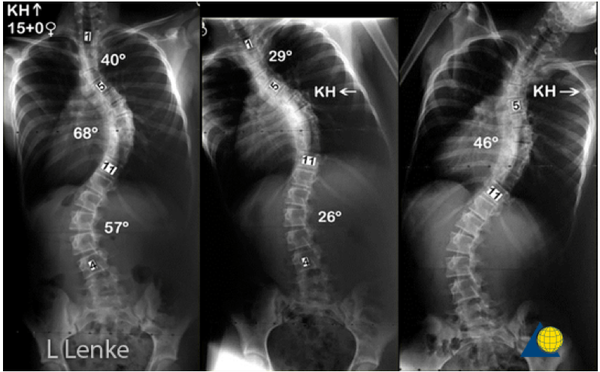

Перед операцией обязательно выполняется рентген. Причем особый. Делаются снимки с захватом всего позвоночника (или всего тела) в двух проекциях спереди и сбоку.

Еще делают снимки с наклонами вбок. Если на этих снимках позвоночник плохо распрямляется при наклоне в сторону дуги, то деформация считается ригидной.

Оценивают идиопатический сколиоз по системе, которую разработал американский хирург Lawrence Lenke. Сейчас это мировой стандарт, она довольно сложна, но ничего лучше пока не придумали.

Классификация Василия Дмитриевича Чаклина (4 степени, которые ставят в поликлиниках) не годится для предоперационного планирования. Посмотрите на картинке ниже насколько отличаются две деформации с одинаковыми градусами кривизны.

Дело в том, что она не предусматривает то, насколько коротко можно зафиксировать сколиоз. А в хирургии деформаций борются за каждый сегмент, который можно сохранить без фиксации. Это крайне важно.